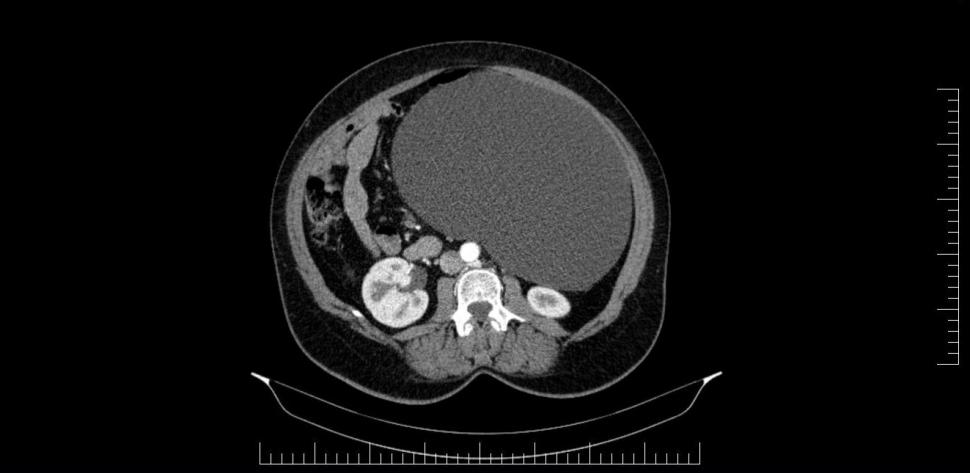

Potrivit reprezentanților Spitalului Militar de Urgență „Dr. Alexandru Augustin” din Sibiu, chistul ovarian de 4,5 kilograme a fost descoperit la o pacientă în urma unui consult ginecologic și a unor investigații în cadrul Laboratorului radiologie și imagistică medicală al Spitalului Militar de Urgență „Dr. Alexandru Augustin” din Sibiu.

Existând suspiciunea de neoplasm, medicul din cadrul Compartimentului Ginecologie din Secția Chirurgie Generală a luat decizia de a extrage formațiunea chistică în întregime.